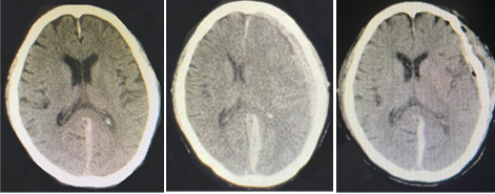

“时间就是脑细胞”!神经外科立即启动应急预案,大家各司其职,各负其责,紧张、有序地参与抢救。紧急复查头颅CT结果,显示左侧额颞顶部迟发性硬膜下血肿、中线结构右移,脑受压严重,随时存在呼吸、心跳骤停危险,需急诊开颅手术。随即,备皮、导尿、病情沟通、医疗文书签署、备血等等,一切都在争分夺秒地进行。在神经外科副主任、副主任医师应建有的组织下,术前准备快速完善,急诊全麻下为患者实施硬膜下血肿清除术。经过3个多小时的鏖战,手术顺利结束,此时已到了第二天的凌晨。术后患者意识恢复,扩大的瞳孔回缩至正常,复查头颅CT证实血肿清除完全,手术取得圆满成功。

急诊头颅CT;术前头颅CT ;术后头颅CT(图从左至右)